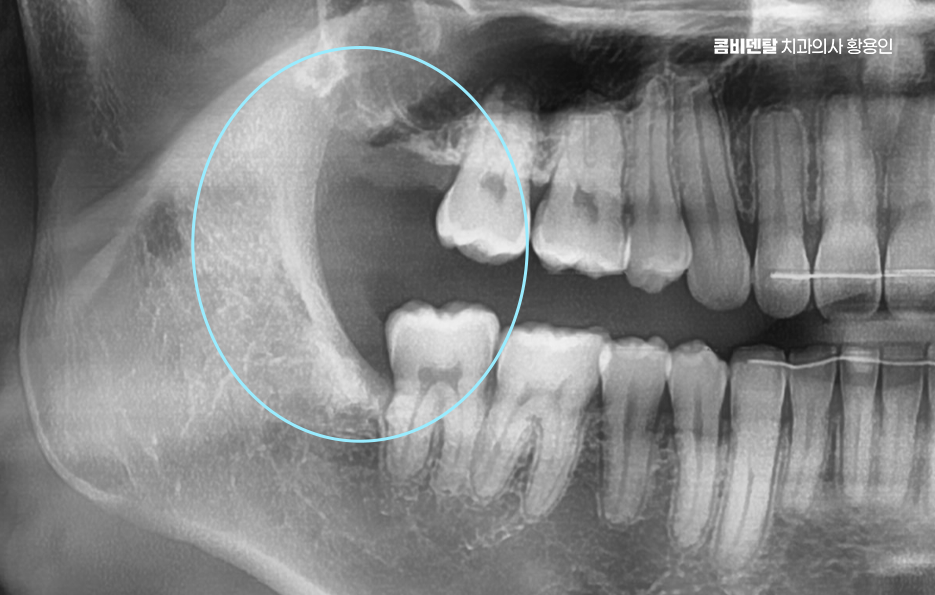

완전 매복사랑니는 보통 아래턱, 즉 하악의 뒤쪽에서 자주 발견되는데 위턱보다는 아래턱 뼈가 더 단단하고 구조적으로 복잡해서 발치 난이도가 더 높을 수 있으며 이 매복된 사랑니는 위치나 각도에 따라서도 발치의 난이도가 달라질 수 있었어요

여기에 더해서 신경과의 거리도 문제로 아래턱에는 하치조신경이라는 굵은 감각신경이 지나가는데 완전 매복사랑니의 뿌리가 이 신경과 가까이 위치해 있는 경우가 많아서 만약 발치 중 이 신경을 건드리거나 손상이 생기면, 입술이나 턱 끝 부위에 감각 이상이 생길 수 있어요.

완전매복사랑니 발치 그래서 무조건 바로 뽑는다고 되는 게 아니라, 사전에 정밀한 진단과 영상검사가 꼭 필요하며 일반적인 파노라마 사진 외에도 CT 촬영을 통해 신경과의 거리, 뿌리의 형태, 턱뼈의 두께 등을 정밀하게 확인해야 발치 계획을 안전하게 세울 수 있었어요.